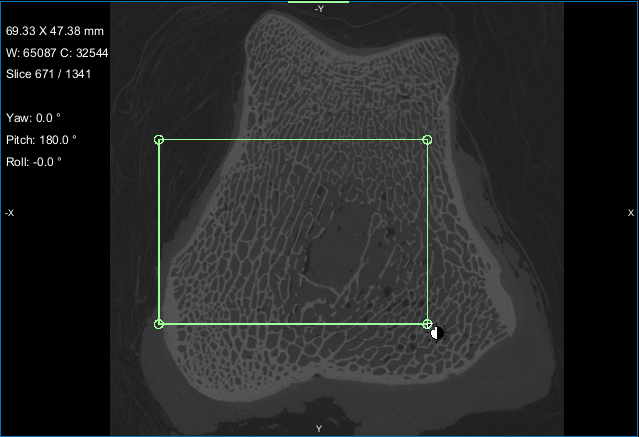

This section of the tutorial describes how to use the Bone Analysis module for 3D volume fraction plotting. You should note that volume fractions are scalar maps.

Comparison of volume fraction scalar map (on left) with vector-based field of anisotropy (on right)

NOTE You can also use any of the boxes you created previously in this tutorial to map volume fraction.

When processing is complete, the volume fraction dataset appears on the Data Properties and Settings panel.

NOTE In most cases, the Jet LUT provides good visualizations of volume fraction.